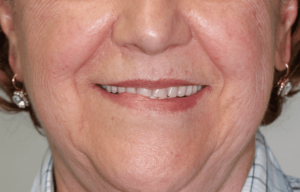

Caso de éxito 2